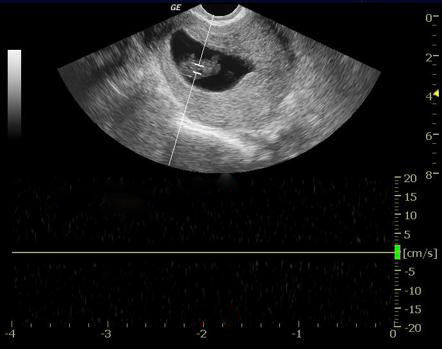

위 초음파 이미지 처럼

자궁 안에

태아(fetal pole)는 보이는데

심 박동은 없어진

계류 유산인 경우

소파술 이후에

산후조리 한약을 원해

많이 내원하십니다.